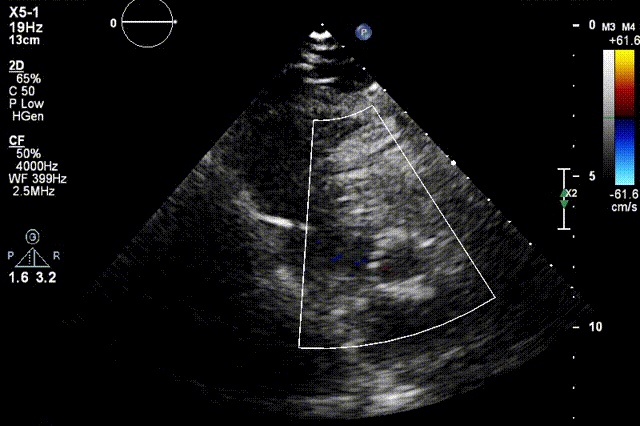

检查结果-术中超声

检查结果-即刻超声

动脉瓣瓣周轻度反流。

经主动脉口收缩期血流最大速度约1.5m/s,最大跨瓣压差约10mmHg。

术后24h心超

● EF 68% 。

● 主动脉瓣未见明显反流。经主动脉瓣口收缩期最大流速约1.9m/s,最大压差约15mmHg,心率约95bpm。

● 二尖瓣轻度反流 。

● 三尖瓣轻度反流,最大反流速度约2.9m/s,估测肺动脉收缩压约44mmHg。

● 经左室流出道收缩期最大流速约1.9 m/s。